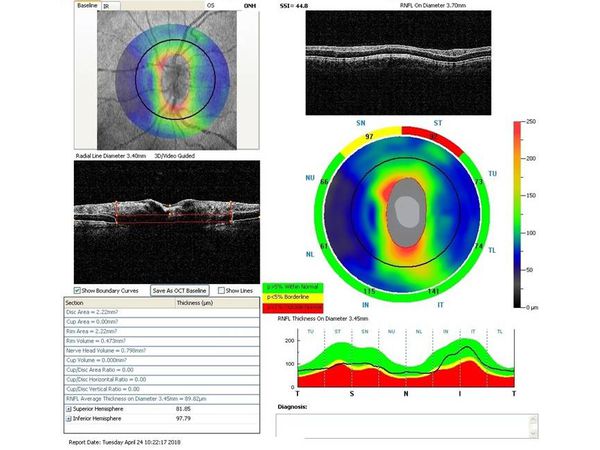

Также при первичном осмотре была проведена оптическая когерентная томография (ОКТ)(рис. 1-4).

Через неделю и через месяц после операции пациентка приходила на осмотры для проверки внутриглазного давления, остроты зрения и проведения ОКТ (рис. 5-8).